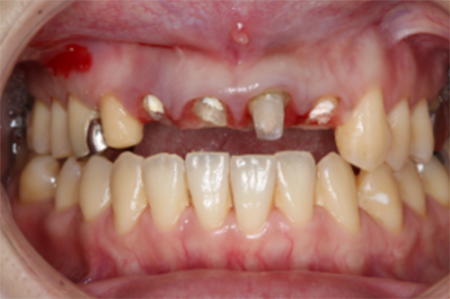

この患者様は長い事歯科医院には通っておらず、下の歯は前歯以外は全て崩壊していることが分かります。

前から見ても歯が欠けてしまい、歯茎も赤く腫れてしまっているのが分かります。

一般的には入れ歯が妥当かと思われますが、患者様は33歳、まだまだ人生は長いです。

奥歯がないと前歯でしか噛めなくなってしまい、残っている前歯もいずれダメになってしまいます。

また、奥歯がなくなってからの期間が長かったため、入れ歯が入るスペースが奥にないのが分かります。

様々なことを鑑み、患者様とも何度も話し合いを行い、下の奥歯には必要最低限のインプラントを、他の歯も外科処置を施しなるべく歯を抜かない方法を取りました。

最終的に抜歯した本数は下の歯5本。上の歯に関しては全て残すことが出来ました。

奥歯があることで前歯の負担を減らし、前歯を失うリスクを下げることが出来ます。

| 治療期間 | 2年 |

| 費用 | 歯周外科治療 3万円×17本 GBR 15万円×2部位 インプラント 37万円×4本 補綴 ジルコニアクラウン 15万円×24本 |